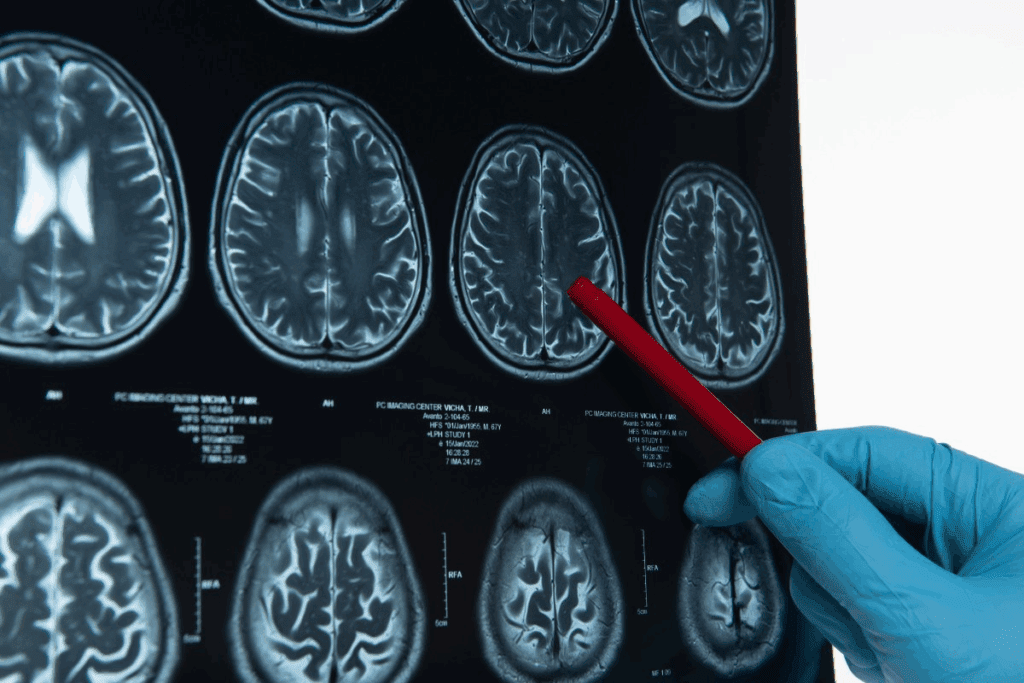

Imaging Techniques

Imaging tests are the main tools for finding brain metastases. Magnetic Resonance Imaging (MRI) is very useful because it shows the brain clearly. It helps see how big and where the tumors are, which is important for treatment planning.

Computed Tomography (CT) scans and Positron Emission Tomography (PET) scans are also used. CT scans spot bigger tumors and are good in emergencies. PET scans show how active the tumors are, helping to see how aggressive they are.